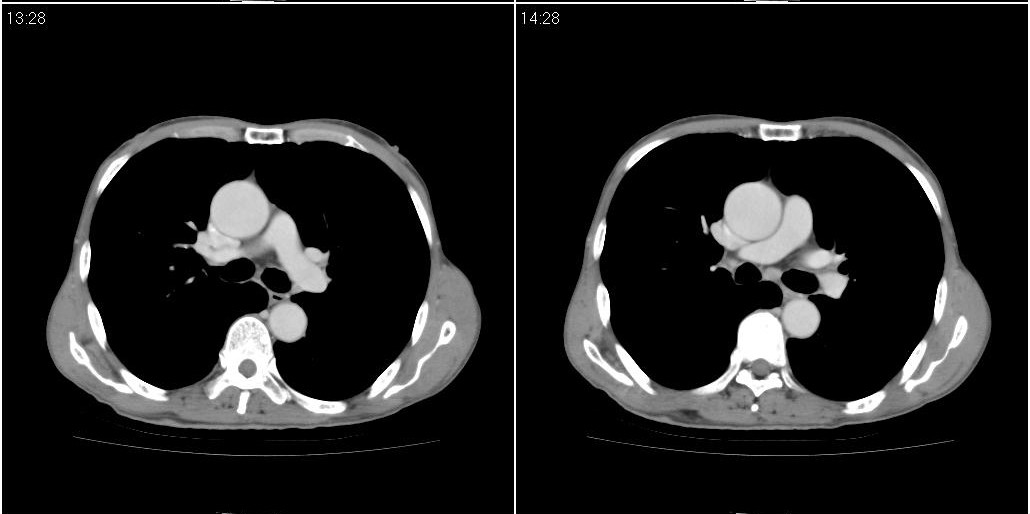

考虑右肺中叶感染。左肺下叶支扩。

右中肺阻塞性炎症,建议纤支镜!双下支扩感染。

1)右肺中叶慢性炎症并支气管扩张,节段性肺不张。2)两肺下叶支气管扩张。